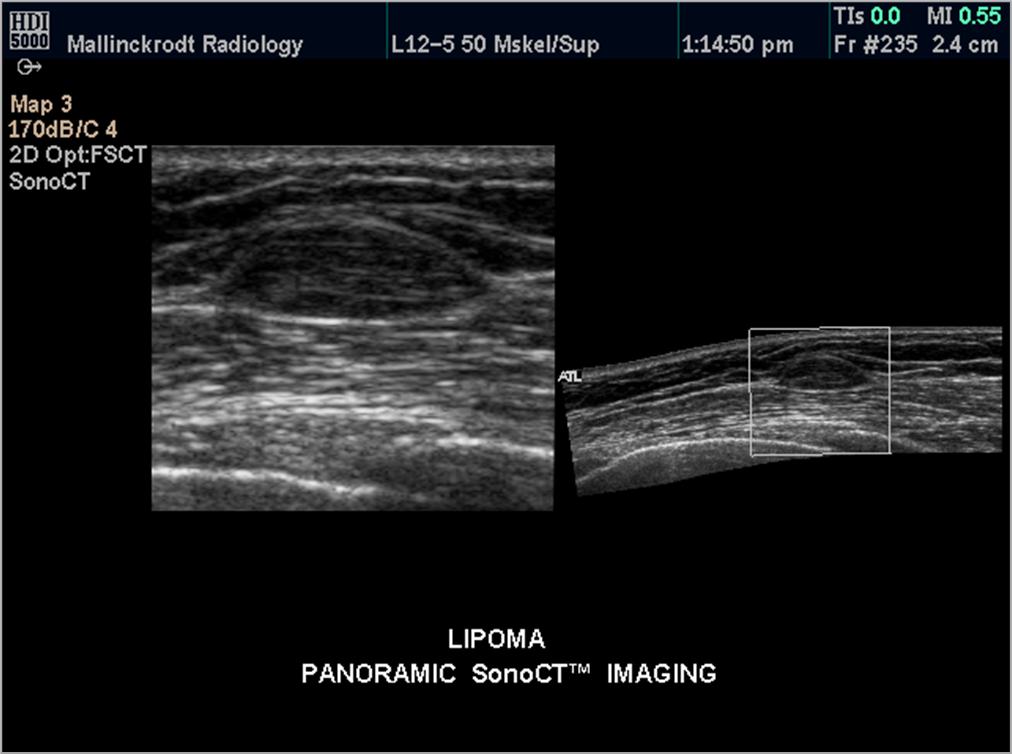

What is this image showing?

lipoma

What is a lipoma?

fatty tumor

-encapsulated fat cells

What are the sonographic features of a lipoma?

-isoechoic

-smooth borders

difficult to see on ultrasound